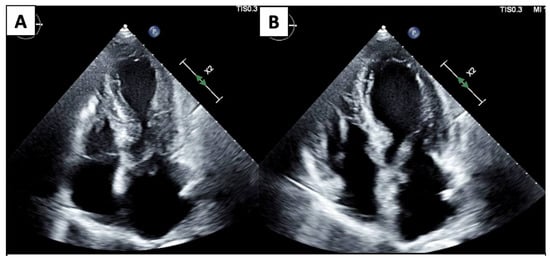

| Imaging Modality | Imaging Illustrations | Description |

|---|---|---|

| Echocardiography | ![]() | Mild left-ventricular dilation and systolic dysfunction |